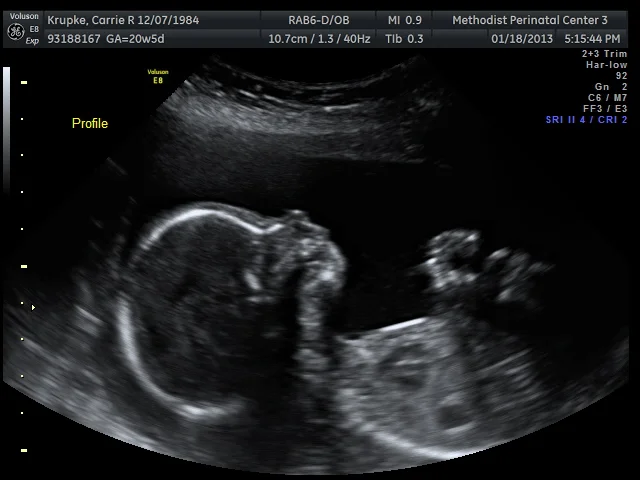

A great profile, but boy, did Baby make the tech work hard from there on out! In true Williams style, Baby was working on it’s flip turns the entire time I was on the table. Which, originally, should’ve been 45 minutes, but ended up being a whopping 75! Think of it as the best 75 minute TV show you’ve ever watched. And yes, that includes Downton Abby. 😉 Our first tech was a student who was weeks away from graduating and the full-time tech was watching the print-outs from another room. The student’s first comment was how beautiful Baby’s heart was. (And that was when mine melted.)

“Nope, that’s the hamburger!” And there was much rejoicing. I’ll follow my DAUGHTER’S lead and respect her modesty that she so stubbornly protected for over an hour and not show that revealing image, but you look at her profile a little differently now. Knowing it’s a girl, don’t you? 🙂